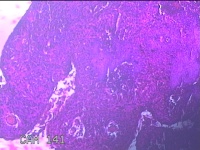

宫颈6点、12点组织

性别

女

年龄

57岁

临床诊断

子宫颈上皮内瘤变[CINⅢ级];子宫颈肿瘤

一般病史

阴道不规则出血1年。

标本名称

大体所见

1.“宫颈6点组织”:灰白粉红色组织1.3x0.8x0.3cm一块。 2.“宫颈12点组织”:灰白粉红色组织1.5x0.7x0.2cm一块。